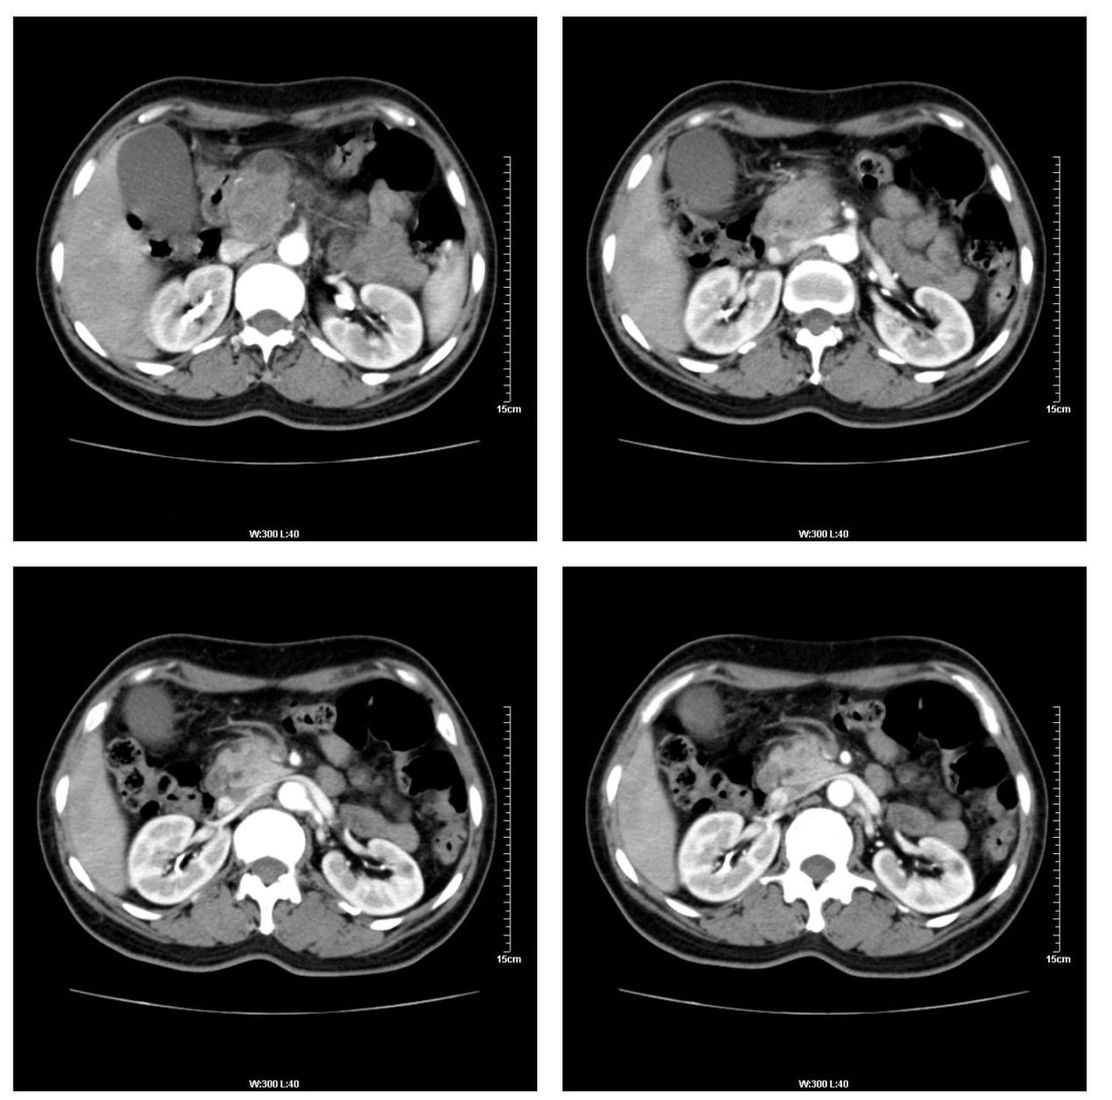

标题: CT13800:女性,52岁。腹痛、腹胀、消瘦及乏力5个月。 [打印本页]

标题: CT13800:女性,52岁。腹痛、腹胀、消瘦及乏力5个月。

考虑胰腺导管内乳头状黏液肿瘤.建议mri

考虑胰腺囊腺癌。

以下是引用张嘉航在2008-6-2 19:29:00的发言:[br]考虑胰腺导管内乳头状黏液肿瘤.建议mri

支持!

支持

考虑胰头癌可能。

考虑胰头癌可能性大。